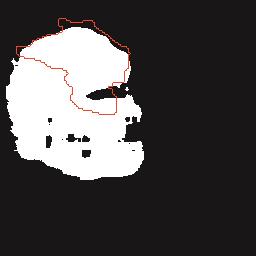

乳腺癌是全球女性最常见的恶性肿瘤之一,准确的病变分割对于乳腺癌的早期诊断与治疗具有重要意义。然而,由于病变形态的多样性以及超声成像机制的复杂性,现有基于深度学习的乳腺超声图像病变分割方法在分割准确性方面仍面临巨大挑战。为进一步提升乳腺超声图像中病变区域的分割精度,该文基于经典U-Net架构,提出了一种新型乳腺超声图像病变分割网络(CWSASKM-BBAM-Net)。首先,在网络中引入逐通道空间自适应选择核卷积模块(CWSASKM),根据不同通道的语义特征为每个空间位置自适应选择感受野大小,以增强多尺度信息的建模能力;然后,引入双向边界感知机制(BBAM),通过融合正向与反向注意力,对目标显著区域及其边界进行协同建模,同时逐步提升对非显著区域与病变区域的区分能力,以进一步强化边界信息的表达;最后,在3组公开乳腺超声图像数据集(BUSI、UDIAT和STU)上开展分割实验。结果表明:该方法在数据集BUSI上的杰卡德指数、精确率、召回率和Dice相似系数分别为71.97%、82.85%、81.40%和80.44%,较次优方法分别提升1.69、1.05、1.28和1.84个百分点;在数据集UDIAT上,这4项指标分别达到78.14%、88.31%、86.73%和86.10%,较次优方法分别提升了2.75、2.04、0.56和2.01个百分点;在外部数据集STU上,该方法也取得了优于其他方法的整体表现。实验结果表明,CWSASKM-BBAM-Net在乳腺超声图像分割任务中展现出更优的整体性能。